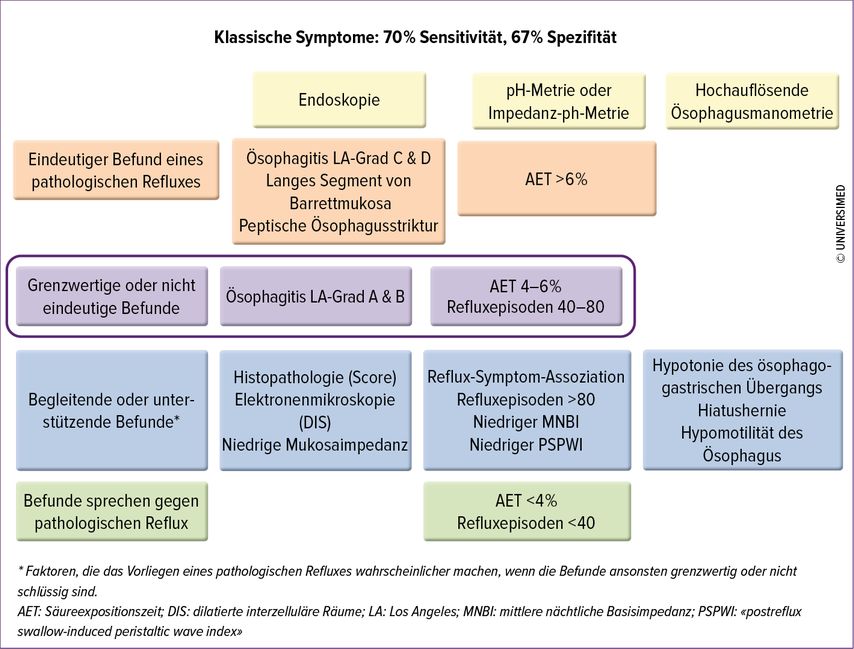

Indikationen für eine Langzeit-pH-Metrie

70–90% der Patienten mit Refluxsymptomen haben bei der initialen Endoskopie einen unauffälligen Normalbefund. Dies kann an einer konkomittierenden PPI-Therapie, einer nach PPI-Therapie abgeheilten erosiven GERD liegen oder einer nicht erosiven Refluxerkrankung entsprechen. Differenzialdiagnostisch ist in diesem Fall aber auch an eine Refluxhypersensitivität («hypersensitiver Ösophagus») oder das Vorliegen einer funktionellen Dyspepsie, z.B. vom Typ «epigastrisches Schmerzsyndrom» zu denken. Um dies zu diagnostizieren, sollte eine 24h-Impedanz-pH-Metrie erfolgen. Diese ist auch bei typischen Refluxbeschwerden ohne Besserung auf eine bereits begonnene PPI-Therapie oder bei atypischen oder extraösophagealen, z.B. respiratorischen Beschwerden indiziert und sollte stets vor einer geplanten Antirefluxoperation erfolgen, um den Reflux und die Symptomatik zu quantifizieren und damit die OP-Indikation zu objektivieren. Zur Überprüfung der Diagnose sollte die Untersuchung ohne PPI-Therapie erfolgen, da die Aussagekraft der Methode dann höher ist und mehr Patienten mit einer signifikant positiven Symptomkorrelation identifiziert werden können. Für die Untersuchung wird ein 2–3mm dünner Impedanz-pH-Metrie-Katheter transnasal in den proximalen Magen eingeführt. Neben dem Magen-pH wird über eine weitere pH-Elektrode, die sich 5cm oberhalb des zuvor manometrisch (s.u.) identifizierten unteren Ösophagussphinkters befindet, die Säureexpositionszeit im distalen Ösophagus bestimmt. Impedanzsensoren auf verschiedenen Höhen des tubulären Ösophagus erlauben die Untersuchung des Bolustransports und die Unterscheidung von Schlucken, Luftschlucken oder Refluxepisoden und Luftaufstossen. Dabei ist die Abgrenzung vom sog. «supragastrischen Aufstossen» («supragastric belching») von besonderer Bedeutung. Hierbei handelt es sich um eine Atem-/Verhaltensstörung, bei der Patienten aktiv, aber unbewusst, Luft in den Ösophagus einschlucken und unmittelbar darauf wieder aufstossen, was zu einer Triggerung von sauren Refluxepisoden führen kann. Davon abgegrenzt werden müssen das «Luftschlucken», die Aerophagie, und das Aufstossen von Luft aus dem Magen («gastric belching»).

Die Vorteile der 24h-Impedanz-pH Metrie liegen in der Evaluation des Bolustransports im Ösophagus ohne jegliche Exposition gegenüber Röntgenstrahlen und der möglichen Refluxdetektion aller Refluxtyptypen (sauer, nicht sauer, Luft), gegebenenfalls auch unter PPI. Hauptnachteil der Methode ist der häufig als unangenehm empfundene transnasal eingeführte pH-Metrie-Katheter, der die Patienten teilweise in der Wahrnehmung eines üblichen Tagesablaufs doch stärker beeinträchtigt, sodass nicht immer repräsentative Messergebnisse erzielt werden. (Abb. 1)

Abb. 1: Diagnose der gastroösophagealen Refluxerkrankung gemäss Lyon Consensus (nach Gyawali et al., 2018)11